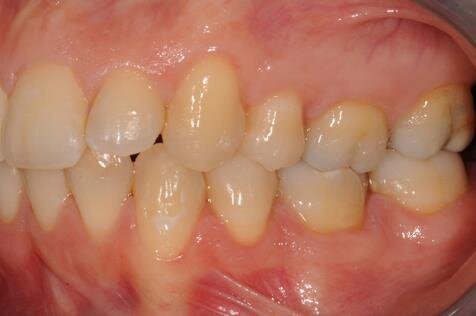

All’esame clinico del viso si osservava una sostanziale simmetria bilaterale e corrette proporzioni facciali verticali frontali e laterali (Figg. 1a-1c). Il sorriso presentava un’adeguata esposizione degli incisivi superiori e dei corridoi buccali e la centratura della linea mediana superiore rispetto al volto. All’ispezione del cavo orale, invece, si riscontrava una lieve deviazione della linea mediana inferiore verso destra di circa 1 mm, con contestuale II Classe canina a destra (Figg. 2a-2c). La mancanza del primo molare inferiore di destra aveva prodotto lo spostamento mesiale, la mesio-inclinazione del secondo e terzo molare inferiore e l’estrusione del primo molare superiore. A sinistra, invece, era riscontrabile una I Classe canina e molare. Erano presenti un moderato affollamento nell’arcata superiore ed un lieve disallineamento degli incisivi inferiori. L’overjet era lievemente aumentato e l’arcata superiore appariva lievemente contratta, soprattutto a destra. Erano presenti recessioni gengivali multiple.

Figg. 2a-2c - Foto intraorali pretrattamento: visioni frontale (a), laterali (b).